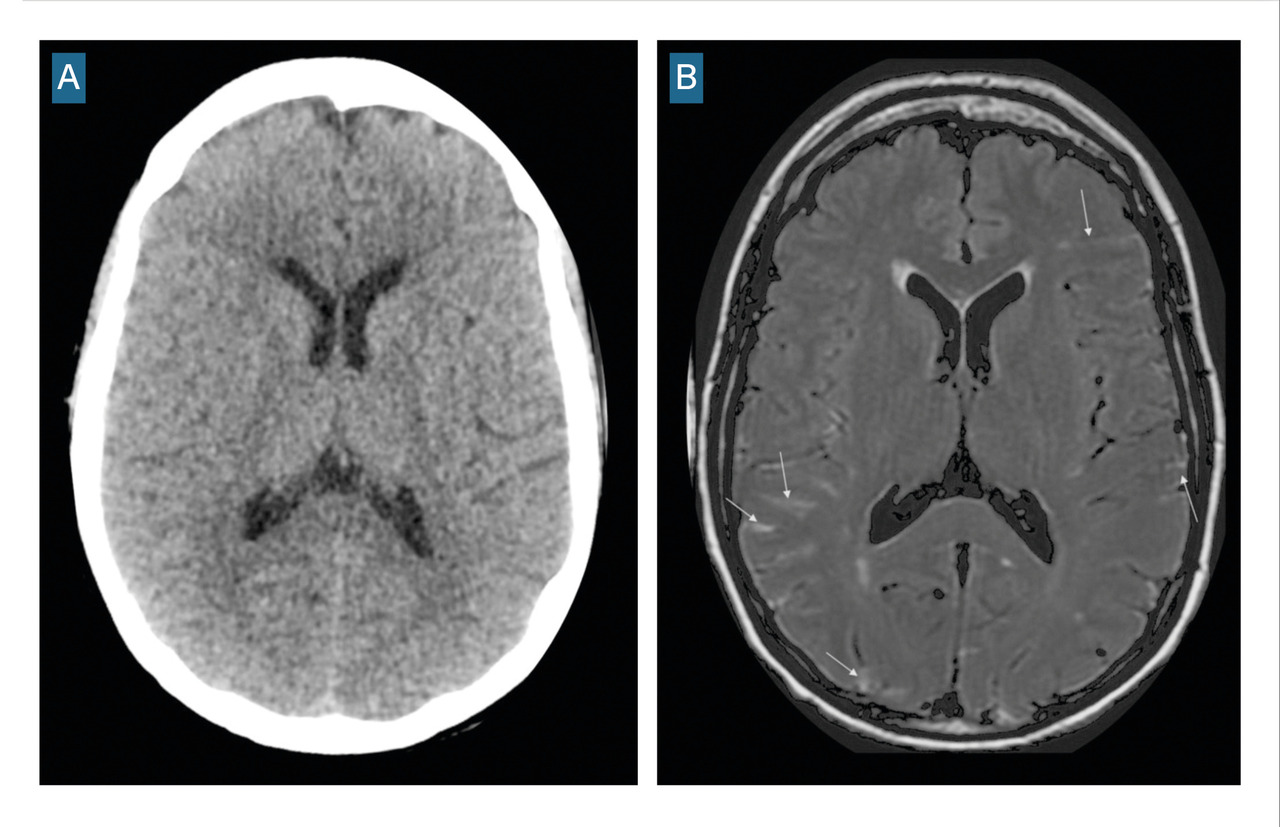

Le scanner doit être réalisé en urgence. Il montre une hyperdensité des espaces sous-arachnoïdiens, évalue la sévérité par l’échelle de Fisher et recherche les complications précoces (fig. 1 et tableau 1).

Si l’IRM est accessible et que l’état du patient est compatible, les séquences FLAIR, T2* ou imagerie pondérée en susceptibilité magnétique (SWI) peuvent remplacer le scanner cérébral sans injection (fig. 2), avec une sensibilité plus élevée pour le diagnostic d’hémorragie méningée.